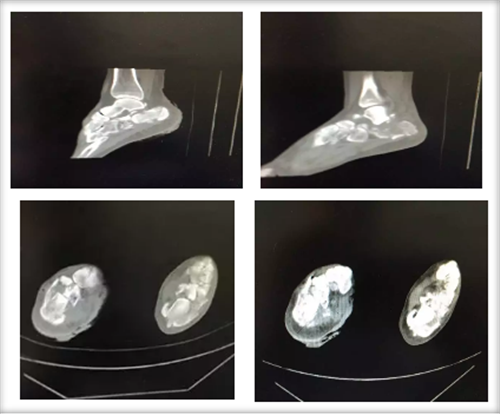

| 2017年11月20日,郴州市第四人民医院骨科主任谭宜昌带领其团队应用3D打印技术成功为一双侧跟骨粉碎性骨折患者实施了手术,术后患者恢复良好。 该患者为一年轻女性,自高处坠落导致双侧跟骨粉碎性骨折,骨折移位较大,为复杂型骨折。对于该疾病使用过去传统影像学方法难以直观了解骨折情况,尤其是年轻医生较难准确对骨折进行评估和分型。模拟手术多在二维图纸或者术者的脑海中进行,在实际手术操作中也只能凭经验进行操作,凭经验选择置入物的规格,并现场将置入物进行折弯、剪裁,调整成较为合适的尺寸。且螺钉方向也只能依靠医生的解剖知识及经验进行确定。这种经验性手术操作准确性较差,过程复杂,耗时长,透视多,创伤大。 而通过3D打印技术将患者术前跟骨CT平扫加三维重建产生的DICOM数据经计算机处理,修改后获得打印模型的标准格式数据,连接3D打印机,根据需要选择不同类型的3D打印技术进行三维物理模型打印。利用该项技术打印出来的骨折模型非常准确,为患者和医生提供了较为直观的触觉与视觉上的体验,能提高医生与患者及家属交流的效果,能为手术方案的设计和制定以及术前演练提供有力的参数和依据,需要多长的钢板,需要几颗螺钉,医生在术前就能心中有数。这不仅大大提高了手术的精确度,提高手术效果,而且还能有效减小创伤,减少术中出血,节省手术时间,缩短患者术后恢复时间,为患者节省医疗费用。

术前CT扫描

3D 打印